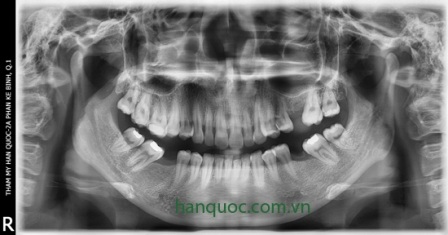

5. Khách hàng được chụp phim X Quang kỹ thuật số Panorama và phim sọ nghiêng kỹ thuật số tại Thẩm mỹ Hàn Quốc số 2A Phan kế Bính . Sau 5 phút, chúng tôi sẽ vẽ và đo đạt đưa ra số liệu chính xác của khung xương cũng như vị trí của các răng bằng công nghệ phần mền vi tính hiện đại sau đó bác sĩ và khách hàng cùng phân tích trên phim đưa ra kế hoạch điều trị chính xác nhất.

Chụp phim X Quang kỹ thuật số Panorama

Đo đạc khung xương đưa ra số liệu chính xác để lên kế hoạch điều trị tốt nhất về phẫu thuật chỉnh nha tại 2A Phan Kế Bính Q1